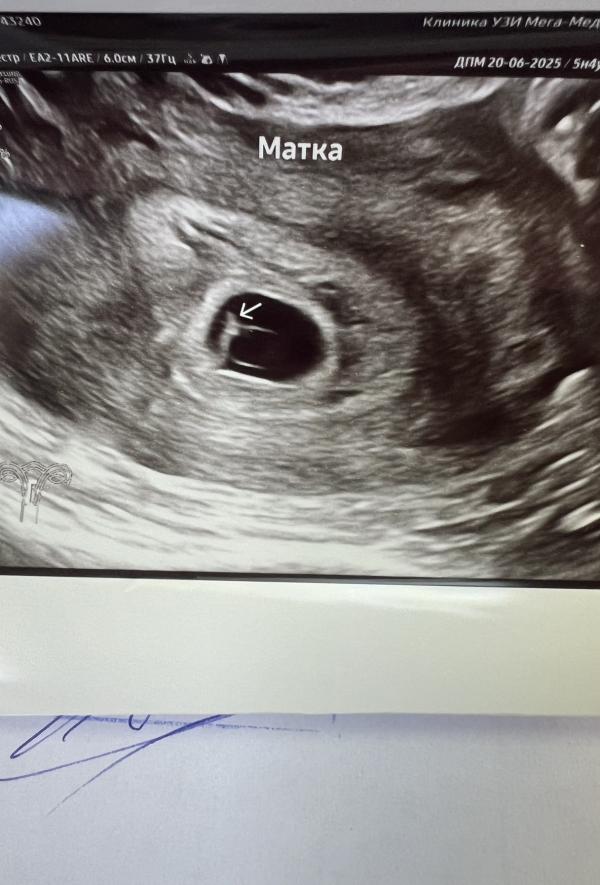

post image 1

post image 2